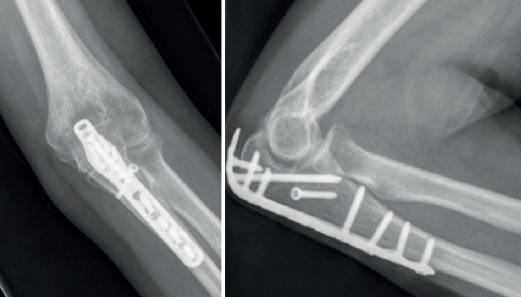

Las placas colocadas en la superficie posterior del cúbito son el sistema de fijación recomendado, proporcionando una fijación más resistente que los cerclajes con agujas de Kirschner y además permiten la fijación adicional de los fragmentos óseos y de la coronoides con tornillos o placas ortogonales en las superficies medial o lateral en los casos con gran conminución metafisaria(1,2,17). Las placas especialmente diseñadas de olécranon (Figuras 5 y 6) o las placas de compresión dinámica de contacto limitado (LC-DCP) de 3,5 mm conformadas para adaptarse a la morfología del cúbito son preferibles a las placas semitubulares, al aportar una fijación más estable(2,18,19).

Cuando la fractura del olécranon incluye una fractura de la coronoides, la reducción y la fijación de esta es condición imperativa para conseguir la estabilidad humerocubital (Figuras 7, 8 y 9). La reducción puede llevarse a cabo a través de la fractura del olécranon o por medio de un abordaje medial, separando o a través de la musculatura flexora/pronadora, teniendo identificados y protegidos el nervio cubital y el fascículo anterior del ligamento colateral medial. En los casos en los que es necesario realizar la sustitución de la cabeza del radio por una prótesis, también es posible el acceso lateral a la fractura de la coronoides. En general, el fragmento permite la fijación con tornillos desde posterior a anterior, a través de la placa posterior o independientes de esta, o en ocasiones desde anterior a posterior. La utilización de placas de 2,7 mm o específicas de coronoides, y técnicas de suturas no reabsorbibles atadas sobre el cúbito proximal o sobre la placa de fijación del cúbito son otras opciones(13,17). Para los grandes defectos óseos o fracturas irreconstruibles de la coronoides, se han descrito injertos óseos de la cresta ilíaca e injertos osteocondrales de la cabeza del radio con resultados impredecibles debido a la osificación heterotópica y a la reabsorción ósea del injerto(20,21).